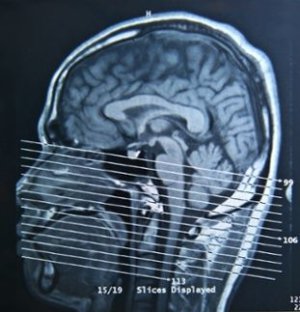

Для успішного лікування черепно-мозкової травми необхідно правильно і вчасно поставити діагноз. Якщо спиратися лише на зовнішні ознаки, за струс можна прийняти забій головного мозку і більш небезпечні травми: тріщини в черепі і крововиливи. Щоб не сталося такої помилки, потрібно негайно їхати в лікарню на рентген. Незайвим буде звернутися до невропатолога.

Велику допомогу в діагностиці складуть слова очевидців або самого потерпілого про те, як стався удар. Однак хворий може просто не пам’ятати, що з ним сталося. Тому, якщо немає ніяких фактів, крім видимих пошкоджень, проводяться додаткові дослідження:

- Комп’ютерна томографія

- Эхоэнцелография

- МРТ

Це робиться для виявлення структурних уражень мозку, які при струсі мозку відсутні.